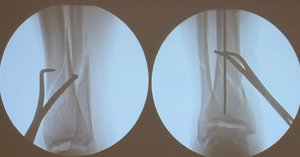

Зокрема, за рік медики виконали понад 200 ендопротезувань колінних і кульшових суглобів, більше 50 трепанацій черепа — у випадках злоякісних інсультів та черепно-мозкових травм та понад 600 операцій при переломах із застосуванням БІОС та МОС.

Окрім цього, щодня медики надавали ургентну та планову допомогу пацієнтам із різною патологією опорно-рухового апарату. Йдеться про ортопедичні операції різної складності — коригуючі остеотомії, вертебропластики, втручання на м’яких тканинах.